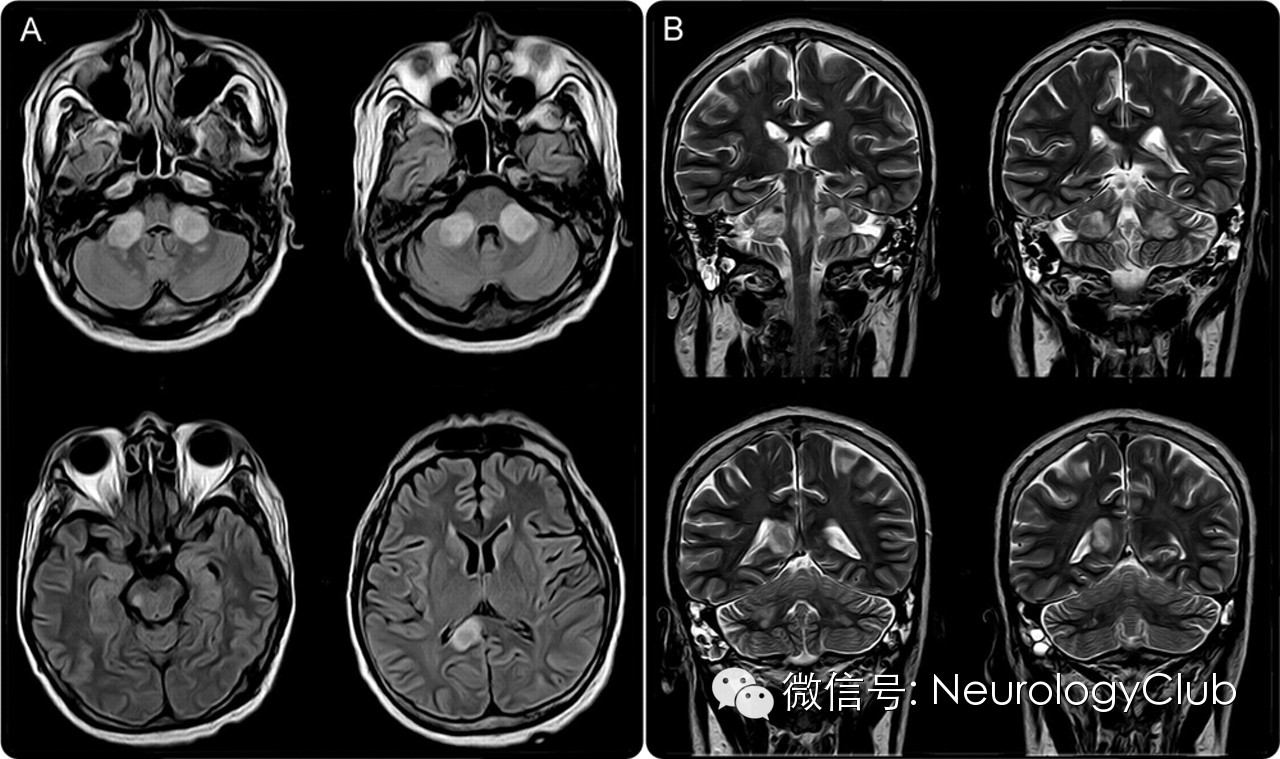

头颅MRI示双侧小脑中脚,右侧大脑脚及右侧胼胝体压部病变。

(A:FLAIR;B:T2WI)